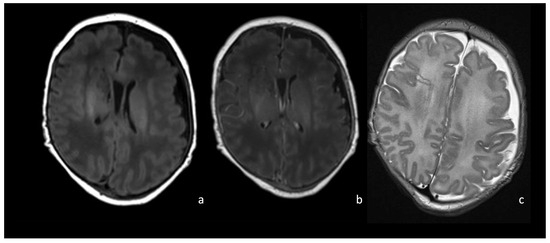

6.1. Cerebritis and Abscesses

- Early cerebritis stage (3–5 days): Bacteria infiltrate the vessels causing vessel wall inflammation and vessel necrosis, which lead to blood barrier disruption and parenchymal invasion. The resulting cerebral infection, namely the early cerebritis, is limited to a focal portion of the brain, does not present a capsule, and presents a coexisting edema. In MRI, early cerebritis is seen as an inhomogeneous and ill-defined area of hyperintensity on T2WI and hypointensity on T1WI, surrounded by edema appearing hypointense on T1WI and hyperintense on T2WI. It presents a diffusion restriction on DWI/ADC in relation to cytotoxic edema and inflammatory hypercellularity. Hemorrhagic foci present as T1WI hyperintense areas within the lesion. After contrast administration, a patchy enhancement is observed, yet no capsule may be identified. On the US, early cerebritis appears as an ill-defined area of inhomogeneous echogenicity presenting increased vascularity on Transcranial Doppler, pairing CT findings, with an ill-defined area of inhomogeneous hypodensity with inhomogeneous and patchy enhancement.

- Late cerebritis (5–14 days): Cerebritis progressively evolves to show a necrotic core and an initial encapsulation. This stage flows into and partly overlaps with the early capsule stage since this last represents a progression with similar, yet more advanced features of the late cerebritis stage. In MRI, the late cerebritis results in a focal formation characterized by a necrotic core, appearing inhomogeneous on both T1 and T2WI, without a complete and regular contrast peripheral enhancement, yet with a defined diffusion restriction on DWI/ADC. On the US, the appearance is similar to the early cerebritis, yet the lesion appears more focal and the core starts becoming hypoechogenic, similar to CT showing a significantly hypodense core in the lesion with irregular and incomplete peripheral enhancement. Early capsule formation (14–30 days): The cerebritis is becoming an abscess since the capsule is evident, yet it is incomplete and thin and appears as a hyperintense rim on T1WI and a hypointense rim on T2WI with contrast enhancement on T1WI.